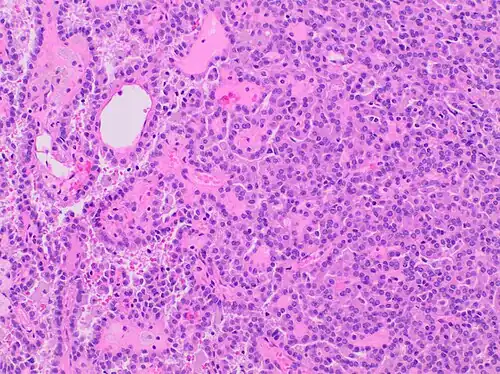

| Papillary renal cell carcinoma, type 1, characterised by tubulopapillary architecture with admixed foamy histiocytes in the papillary cores. | |

Type 1 PRCC, also known as a renal tumor caused by a genetic predisposition of hereditary papillary renal cancer syndrome, compromises approximately 25% of all PRCCs.[14][15] In the perspective of immunochemistry, it has a profile of strong CK7 and alpha-methyl acyl-CoA racemase (AMACR) expression at most focal CA-IX expression.[16] Histologically, its epithelium is composed of relatively small-sized simple cuboidal cells lined in a single layer.[17] These cells are well-characterized by basophilic cytoplasm.[18] Due to its solid growth, an extremely compact papillary architecture is often observed.[16] Other morphological characteristics include intracellular hemosiderin and foamy macrophages placed inside of papillary fibrovascular cores or psammoma bodies.[19] In general, the nuclei of type 1 PRCC belong to grade 1-2 of the Fuhrman system.[16]

A micrograph of type 1 PRCC, illustrating features of small basophilic cells with scarce cytoplasm. A single layer of cells are surrounding the basal membrane.[20] Foamy macrophages are inside of papillary fibrovascular cores. -